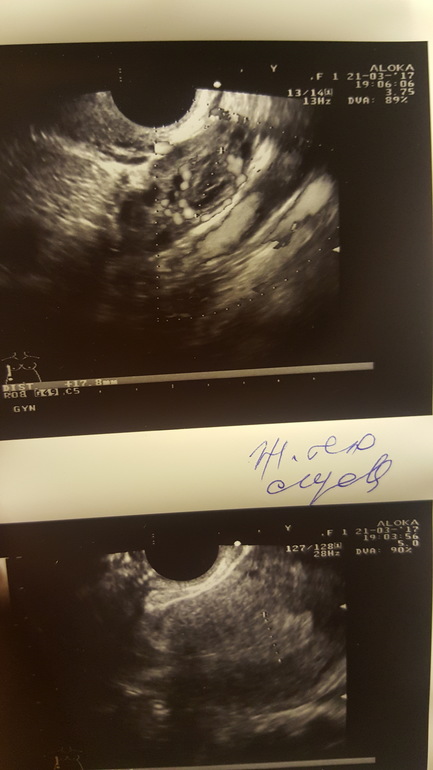

это фолликул 18мм

это желтое тело.

Я лично вообщн не понимаю как она там его увидела)) но она уверенно сразу сказала! А фолликулы я сама на экране видела и понимала что это они)